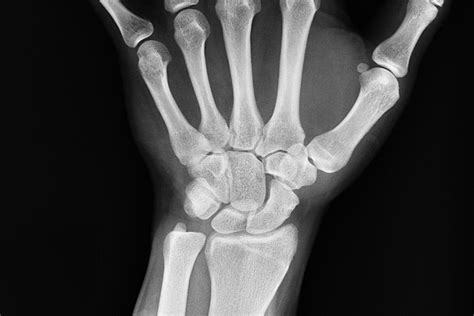

Diagnosing a Broken Scaphoid Bone

Diagnosing a broken scaphoid bone involves a combination of physical examination and imaging tests. A healthcare provider will typically:

• Order imaging tests, such as X-rays, to visualize the bone

However, X-rays may not always show a scaphoid fracture, especially in the early stages. In such cases, additional imaging tests may be required, including:

These tests can provide more detailed images of the bone and surrounding tissues, helping to confirm the diagnosis and assess the extent of the injury.